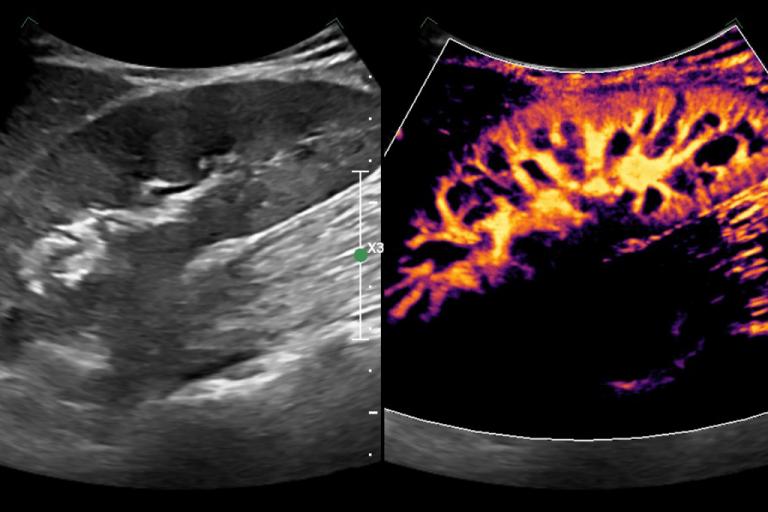

- Impact of Contrast-Enhanced Ultrasound

- Cystic renal masses

- Solid renal masses

- HCC diagnosis and response to therapy

- Quantitative contrast-enhanced ultrasound for organ and tumor perfusion analysis

- Contrast-enhanced ultrasound motion correction and frame filtering